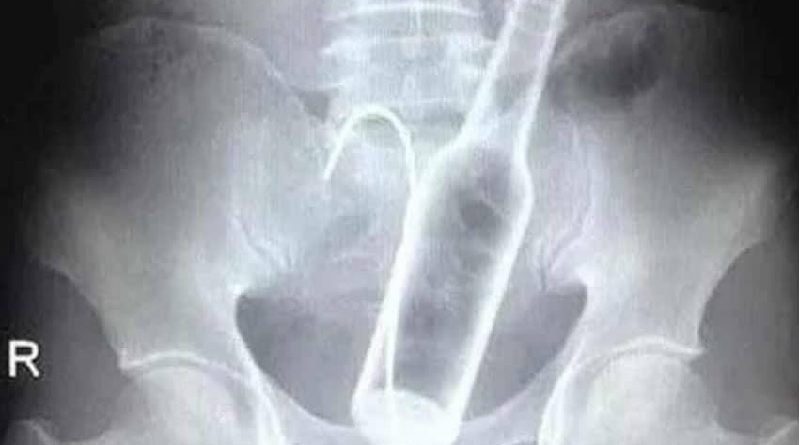

Um homem precisou ser submetido a uma cirurgia na Santa Casa de Poços de Caldas, em Minas Gerais, no último dia 29 de setembro, após dar entrada no hospital com duas garrafas introduzidas no ânus.

Segundo informações divulgadas pela Onda Poços, médicos tentaram remover os objetos — uma garrafa de vidro e outra de plástico — de forma manual, mas o procedimento não teve sucesso. Isso porque uma das garrafas havia se deslocado para uma parte mais alta do intestino, exigindo intervenção cirúrgica.

O paciente passou por uma laparotomia, cirurgia abdominal utilizada para acessar os órgãos internos, e os objetos foram retirados.